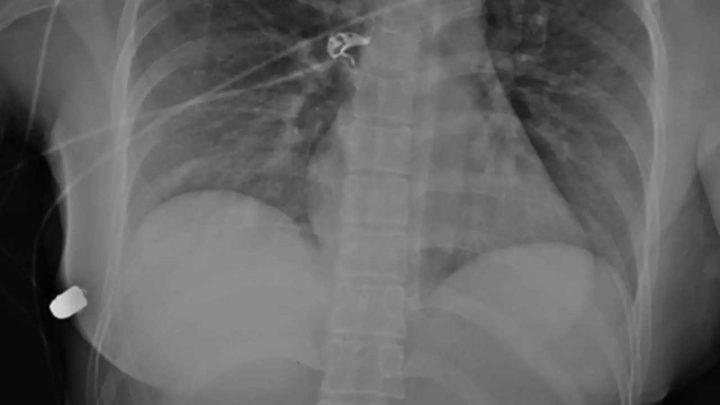

Cette histoire incroyable a fait l’objet d’un article médical très sérieux, publié par l’équipe de chirurgiens américains qui a opéré une jeune femme, victime d’un accident particulier. Elle est arrivée à l’hôpital avec une balle dans la poitrine. La balle était étant entrée dans le thorax, pile à la hauteur du cœur. Lors de l’opération, les chirurgiens ont compris qu’elle ne devait sa vie qu’à ses prothèses mammaires, qui avaient absorbé le choc et dévié la trajectoire de la balle de fusil.

Le docteur Giancarlo McEvenue, chirurgien en chef qui a pris en charge cette patiente particulière, raconte de façons très détaillées, images à l’appui, l’étrange opération qu’il a dû pratiquer. Cette patiente est arrivée en urgence à l’hôpital, après avoir senti une douleur soudaine à la poitrine. Cette Américaine de 30 ans marchait dans la rue quand elle a porté sa main à la poitrine, prise d’une douleur aiguë. Elle a vu que du sang coulait de son sein et qu’elle avait un trou dans la peau. Arrivée à l’hôpital, les médecins ont tout de suite identifié la blessure, celle-ci étant typique d’une plaie par balle. Elle venait d’être victime d’une balle perdue, peut-être tirée par un silencieux, alors qu’elle traversait un quartier fréquenté par les gangs.

Les radiographies ont montré qu’elle n’avait pas grand-chose. Elle avait une côte cassée et malheureusement, sa prothèse était dans un très mauvais état. Les médecins ont décidé de lui enlever les deux prothèses. L’implant gauche avait absorbé la balle et minimisé la blessure. Le coup avait seulement provoqué la fracture d’une côte et l’impact a eu pour effet de lui retourner la prothèse qui s’est retrouvée à l’envers. Au vu du trou dans sa peau et de la position de la balle, les médecins ont conclu que sans la prothèse, la balle lui aurait directement transpercé le cœur. La vie de cette femme « a probablement été sauvée par la déflexion de la balle dans l’implant en silicone », peut-on lire dans l’article médical. Dans la conclusion, le chirurgien indique avoir fait des recherches dans des archives médicales et « étonnamment, il n’y a que très peu de cas de ruptures d’implants provoquées par une arme à feu ».

Crédits : Plastic Surgery Case Stuies/McEvenue